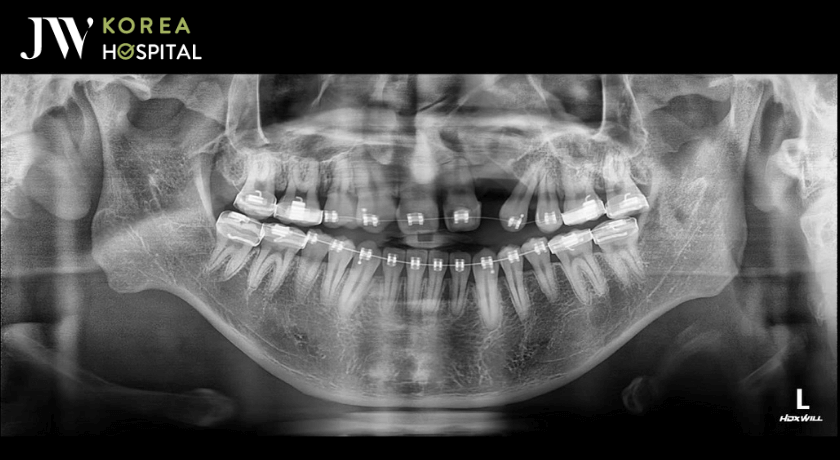

Hình chụp quá trình niềng răng trước khi phẫu thuật hàm

Nam sinh kết hợp Niềng răng – Phẫu thuật Hàm để có gương mặt hoàn hảo